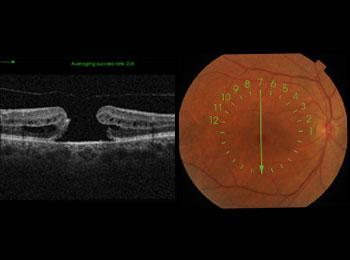

Trou maculaire

Le trou maculaire est une affection qui touche la macula, petite région d’un à deux millimètres située au centre de la rétine. C’est là qu’il y a la plus grande...